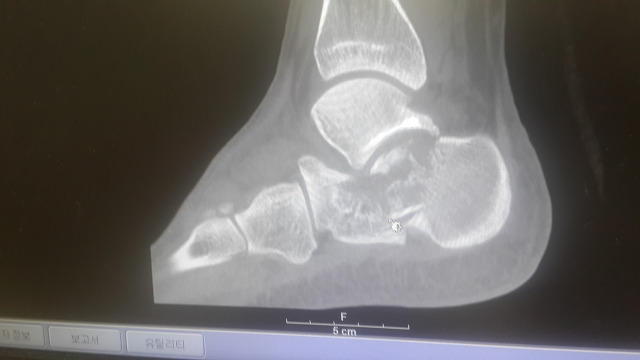

아래는 수술 전 찍은CT 와 X-ray 사진들입니다.

종골이 으스러졌다고 하시더라고요.